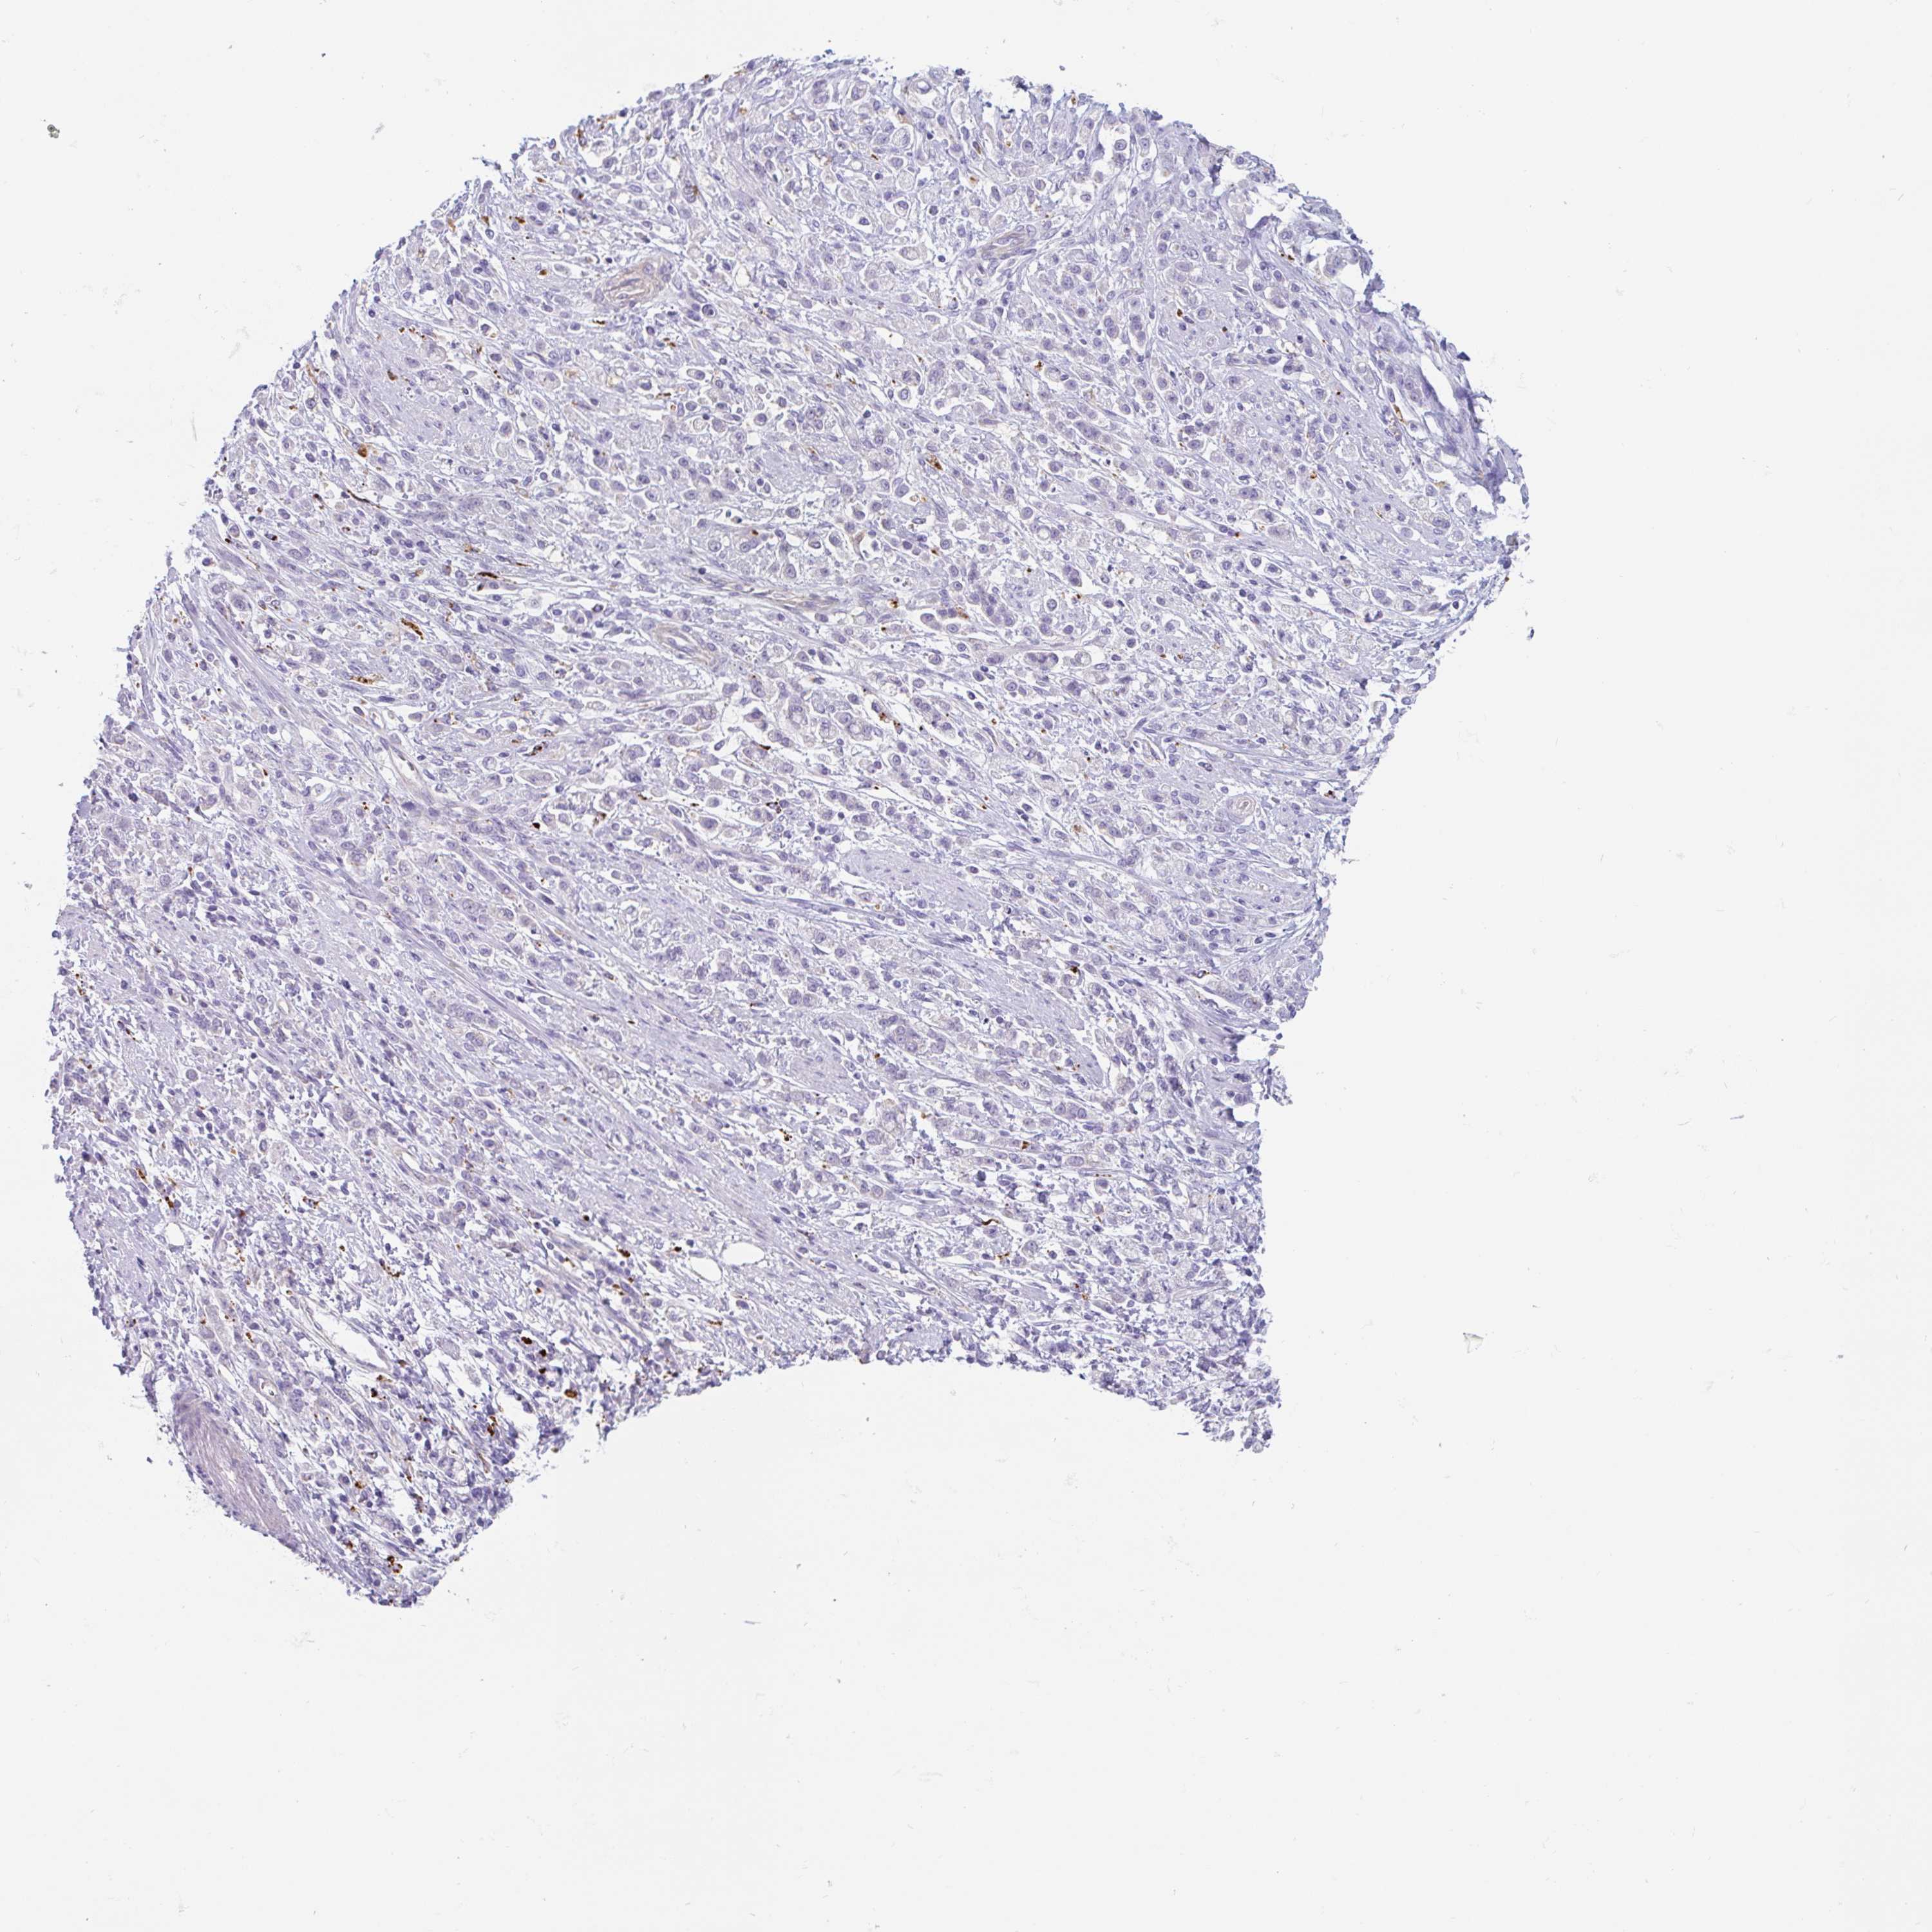

STOMACH CANCER - Protein expressioni

A mouse-over function shows sample information and annotation data. Click on an image to view it in a full screen mode. Samples can be filtered based on level of antibody staining by selecting one or several of the following categories: high, medium, low and not detected. The assay and annotation is described here.

Antibody stainingi

Antibody staining in the annotated cell types in the current human tissue is reported as not detected, low, medium, or high, based on conventional immunohistochemistry profiling in selected tissues. This score is based on the combination of the staining intensity and fraction of stained cells.

Each image is clickable and will lead to virtual microscopy that enables deeper exploration of all samples and also displays staining intensity scores, fraction scores and subcellular localization as well as patient and tissue information for each sample.

Antibody HPA051671

Antibody HPA053556

Staining

High

Medium

Low

Not detected

Intensity

Strong

Moderate

Weak

Negative

Quantity

>75%

75%-25%

<25%

None

Location

Nuclear

Cytoplasmic/membranous

Cytoplasmic/membranous,nuclear

Adenocarcinoma, NOS